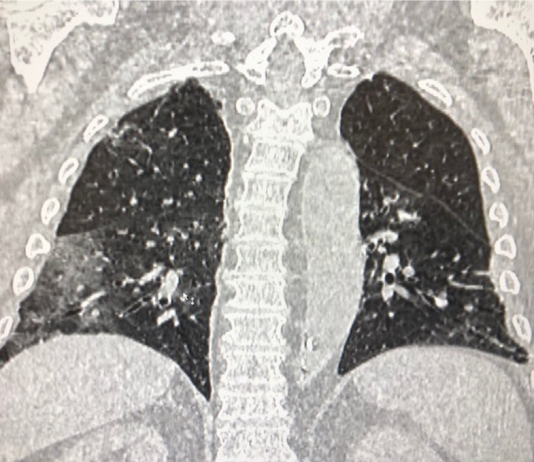

Paziente donna, 44 anni, con anamnesi patologica remota e prossima negative.

Giunge in PS per insorgenza di...